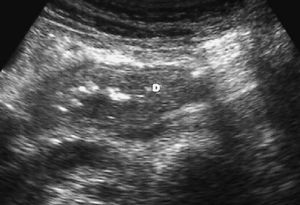

La púrpura de Schönlein-Henoch es una enfermedad autoinmune sistémica provocada por el depósito de complejos inmunes en los pequeños vasos condicionando una alteración en la permeabilidad. Esto se traduce en un rash purpúrico, glomerulonefritis y hemorragia en el tracto gastrointestinal. En la ecografía se puede ver un engrosamiento de la pared intestinal por el hematoma mural con edema mesentérico en la TC13 (fig.6).

Fig. 6--Hematoma de pared. Ecografía que muestra un engrosamiento mural homogéneo de la tercera porción duodenal (D) en un paciente con púrpura de Schönlein-Henoch y dolor abdominal.